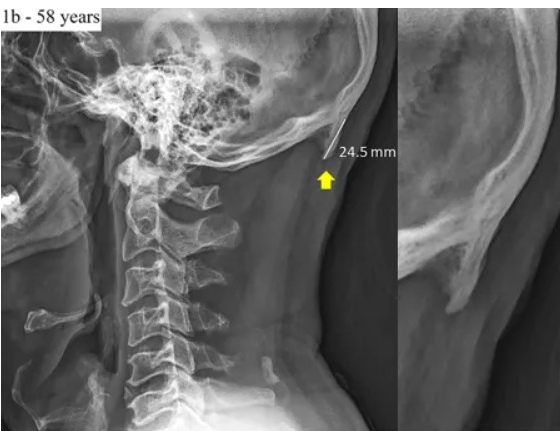

특히 스마트폰을 주로 사용하는 젊은층은 중장년층에 비해 이 부분이 훨씬 더 많이 튀어나온 것으로 확인됐다. 한 예로 연구 대상자인 28세의 한 젊은이의 융기는 2.78㎝인데 반해 58세의 한 중장년은 2.45㎝였다.